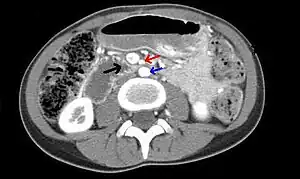

![]() | |

| Abdominal and pelvic computed tomography scan showing duodenal compression (black arrow) by the superior mesenteric artery (red arrow) and the abdominal aorta (blue arrow). | |